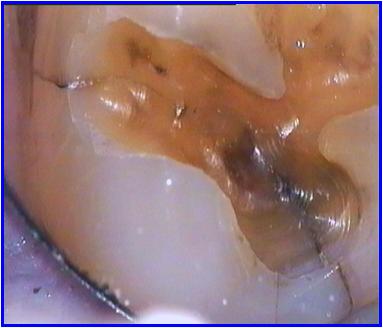

Als oude amalgaamvullingen met behulp van de behandelmicroscoop worden verwijderd, is het opvallend hoeveel (knobbel-)fracturen zich in dergelijke kiezen bevinden.

De indruk bestaat dat (oude mogelijk kierende) amalgaamvullingen voor expansie zorgen die uiteindelijk een kies doen fractureren. Mogelijk dat de randspleet door corrosieproducten wordt gevuld wat voor uitzetting zorgt.